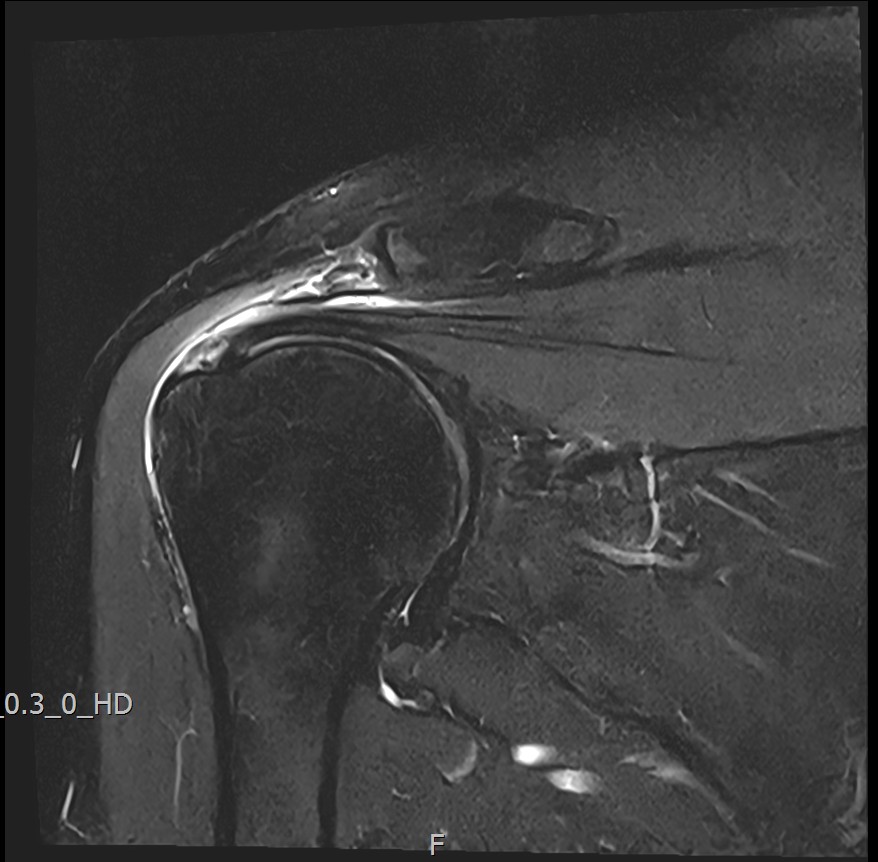

MRI를 검토해보았습니다.

회전근개 극상건의 점액낭면측(bursal-side) 부분파열. 처음보다 파열 범위가 약간 넓어져 있었고, 인대가 얇아진 소견도 보였습니다.

MRI: 극상건 점액낭면측 부분파열

인대 두께: 4.2mm (정상 5~6mm보다 얇음)

1년간 주사치료 3회, 반복 재발